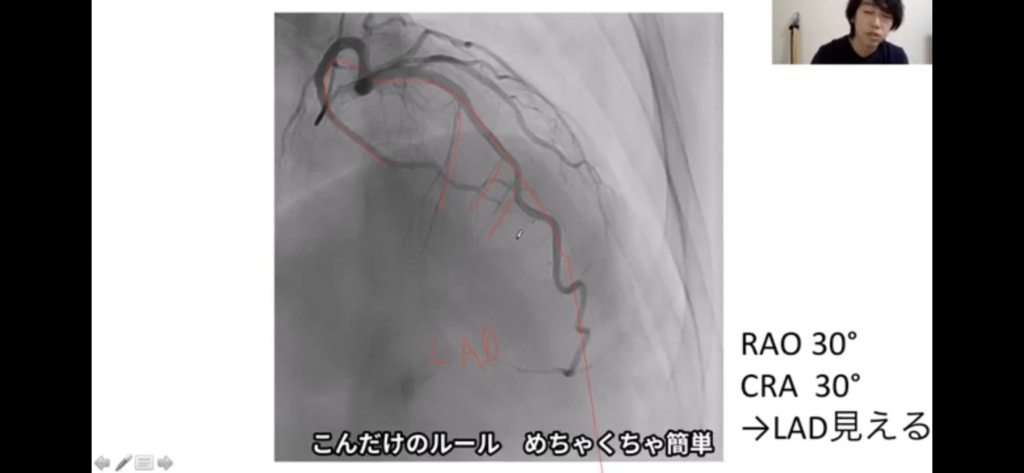

②撮像法は、LAO/CRA(エルクラ)、RAO/CRA(アールクラ)、RAO/CAU(アールコーダル、みぎはら)、LAO/CAU(スパイダー)の4種類

③原則として、CRAは真ん中にLADが、CAUは真ん中にLCXがくる。また、ベクトルが右下に向かっていたらRAO(右からみた図)である。

④エルクラは主幹部から心尖部へのベクトルが、真下に向かうのですぐわかる。

心尖部、真下に向かうのがLAD

↑全体として右下に向かっているのでRAO、全体的に右上にいることからあきらかにCAUではない。CRAだ。心尖までいってるやつがLAD。よくみたら中隔枝ある。

アールクラは、全体的に、右上によってる(ただし、これで判断しないこと)。心尖部までいってるやつがLAD。